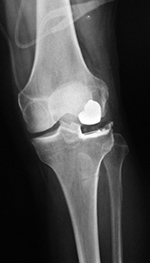

Posterior cruciate substituting total knee prosthesis and patellar resurfacing. |

| 68 year-old woman treated for severe left knee osteoarthritis |

Note the large distal femoral box. There is a surgical drain in the suprapatellar space. |

A posterior-stabilized knee or PCL-substituting knee has removal of the posterior cruciate ligament. This design limits posterior tibial translation in flexion. It contains a posterior cam, deeply dished articular surfaces, plus a third condyle or a central polyethylene post in the posterior middle portion of the tibial insert (figure: cruciate substituting TKA). In flexion this polyethylene post engages a transverse metal cam on the femoral component (Mulcahy, 2013). If the polyethylene post in the tibial insert does not have a metal backing it may not be visible on knee radiography. Usually one can differentiate cruciate-substituting from cruciate-retaining knee arthroplasty

on lateral views. The cruciate-substituting prosthesis often have a larger “box” or thicker femoral component.